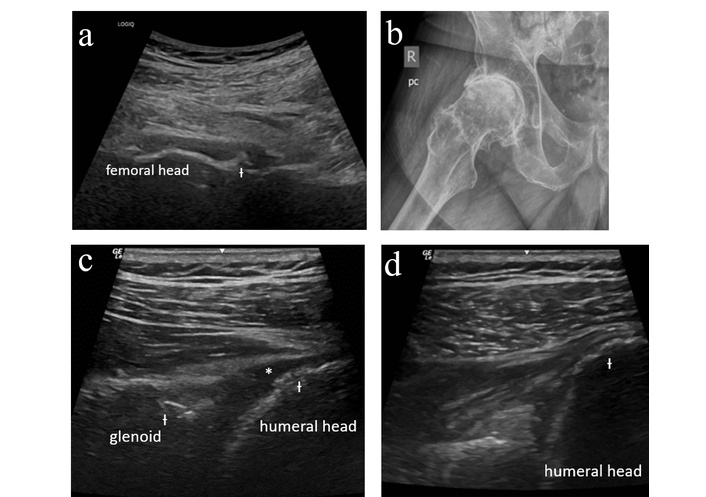

The first case involves a male patient who initially presented at age 73 with new joint symptoms that began approximately 3 weeks after starting treatment for rectal cancer with atezolizumab. He described new pain in his shoulders and right hip as well as aching in the arms and legs. He had a known history of left shoulder osteoarthritis for which he had previously received a corticosteroid injection. On exam, he was noted to have normal shoulder range of motion without evident effusion. No peripheral synovitis was appreciated. Sedimentation rate was mildly elevated at 22 mm/h with normal C-reactive protein. Ultrasound evaluation of the right hip was performed (Figure 1a); he was noted to have advanced degenerative disease without synovitis. Bilateral shoulder and right hip radiographs were obtained, again confirming severe osteoarthritis (Figure 1b).

Case 1 ultrasound images. (a) Right hip anterior longitudinal ultrasound demonstrating femoral head flattening and cortical irregularity (Ɨ) along the femoral neck with no synovitis or joint effusion. (b) Right hip radiograph demonstrating severe femoroacetabular osteoarthritis with joint space narrowing, osteophyte formation, subchondral sclerosis, and cyst formation. (c) Left glenohumeral ultrasound (posterior longitudinal with external rotation) demonstrating cortical irregularity (Ɨ) of the humeral head and glenoid with degenerative labral change, minimally compressible joint effusion (*) (not amenable to aspiration) without proliferative synovitis. (d) Right glenohumeral ultrasound (posterior longitudinal with external rotation) demonstrating cortical irregularity (Ɨ) of the humeral head with no synovitis or joint effusion.

An ultrasound-guided right hip steroid injection was performed. He was advised to begin celecoxib and gabapentin with initiation of physical therapy once pain had improved. He later returned for ultrasound-guided bilateral glenohumeral joint injections (Figure 1c–d). At his last follow-up visit, he described significant improvement in pain.

This case demonstrates the utility of MSKUS in excluding inflammatory features and confirming the presence of degenerative change and as such diagnosing “activated osteoarthritis,” which is a condition in which patients develop new or worsening pain in a joint affected by preexisting osteoarthritis following initiation of ICI treatment. Without ultrasound, this patient’s presentation may have been mistaken for a polymyalgia rheumatica-like presentation, resulting in unnecessary exposure to systemic steroids or other immunosuppressive treatment.